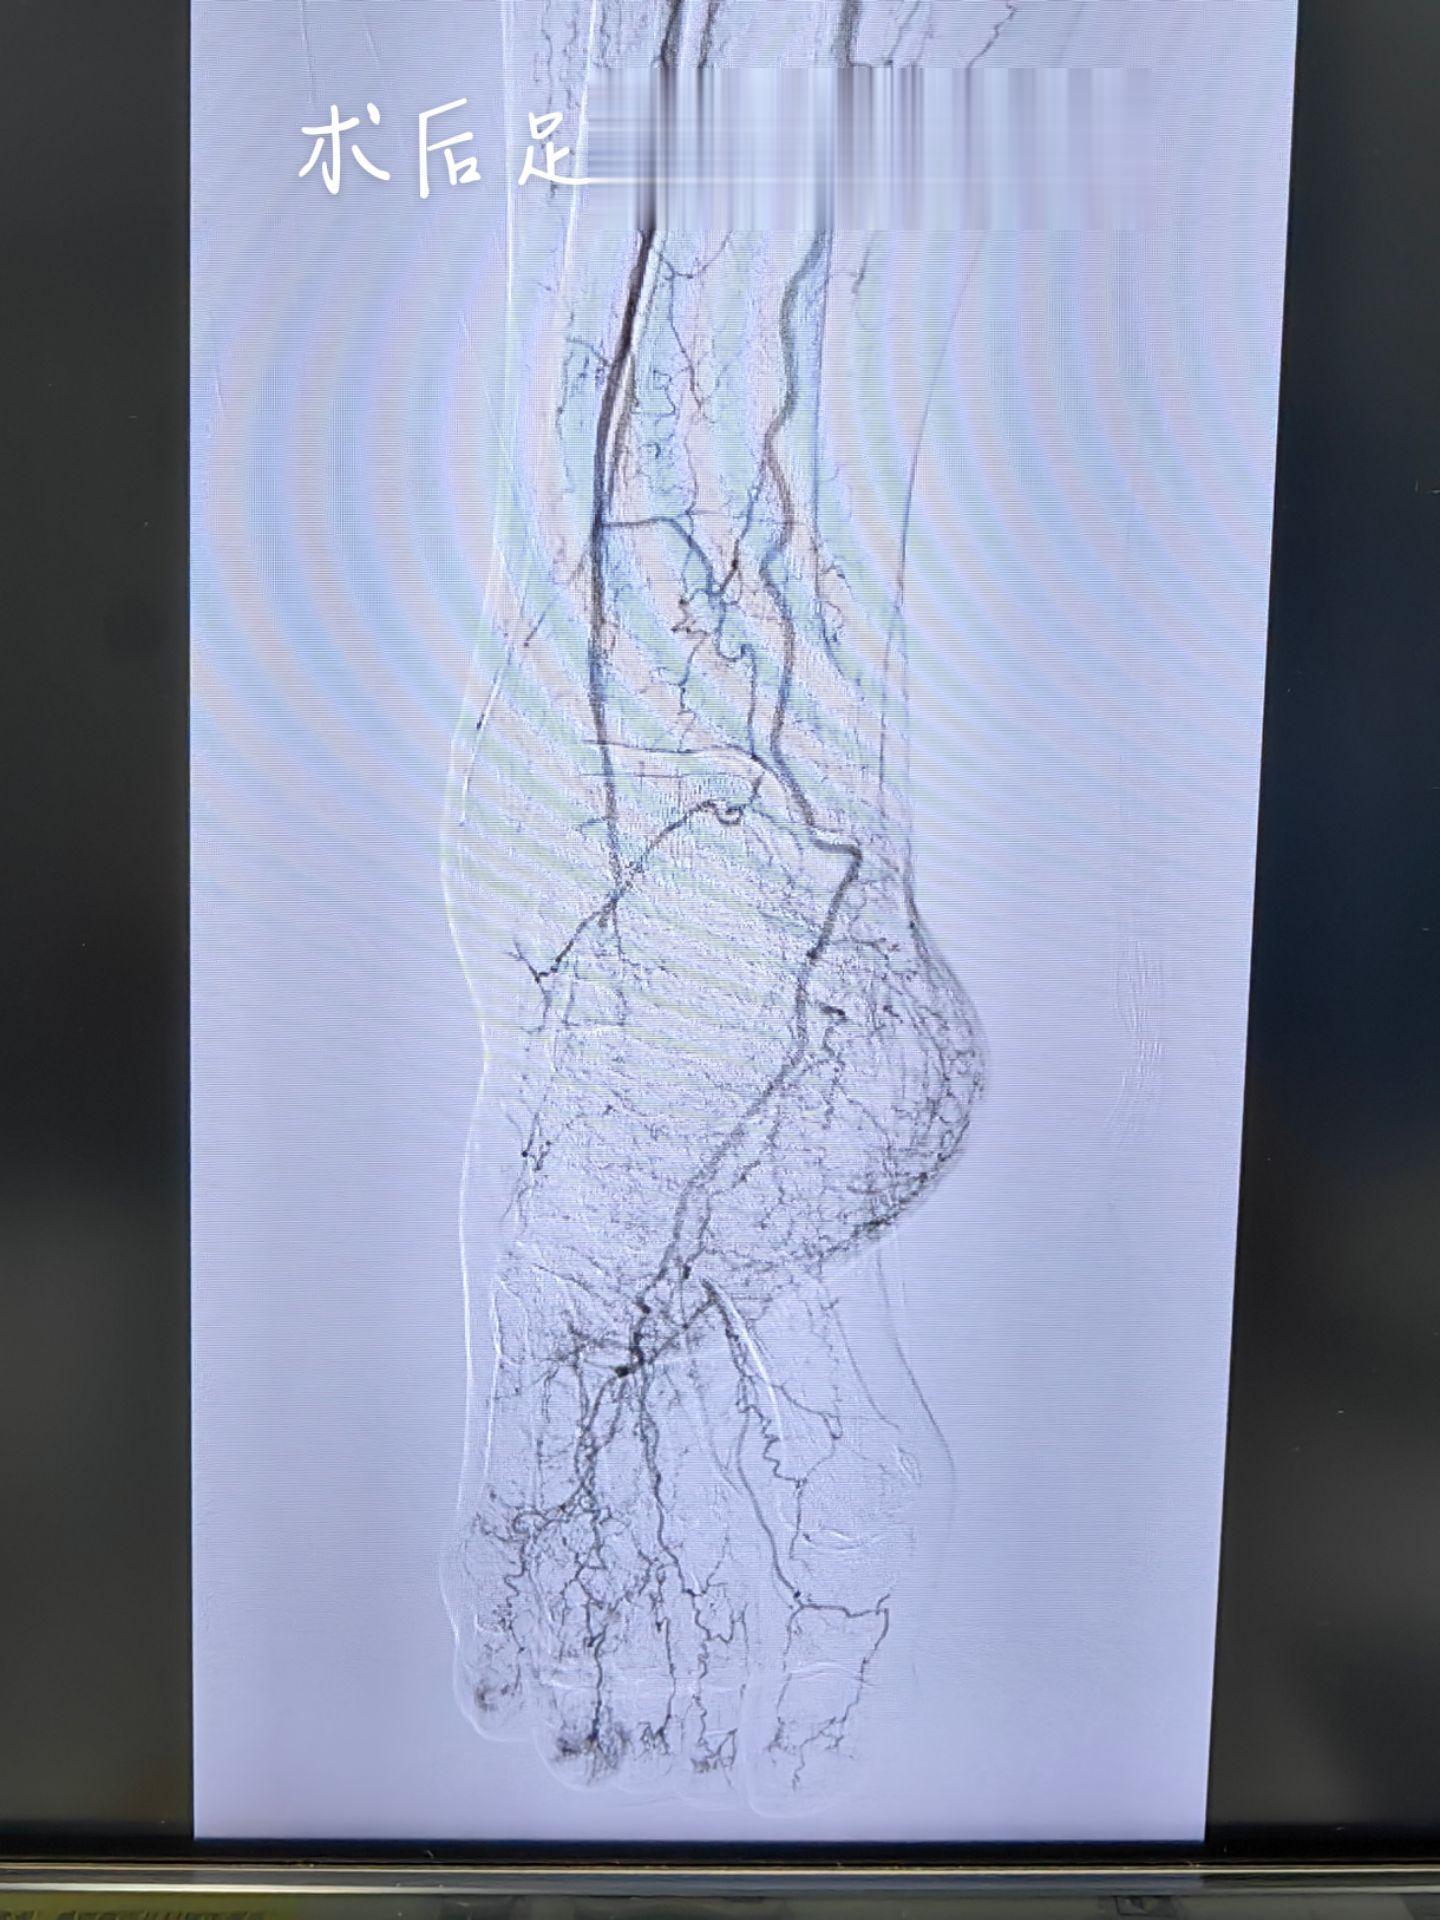

房颤心房血栓脱落引起下肢动脉栓塞,下肢冰冷、发绀,不及时处理会导致下肢坏死截肢,当地没有治疗条件,通过网络医疗联系到我,今天加台开通血管,冰冷发绀的下肢转为温暖红润,保肢成功[胜利